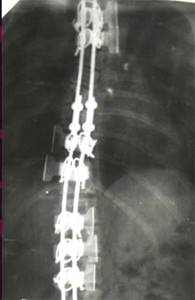

| Больной П-ко, 15 лет Поясничный сколиоз III степени |

Результат оперативного лечения |

| Больная Л-ч, 12 лет сколиоз IV степени |